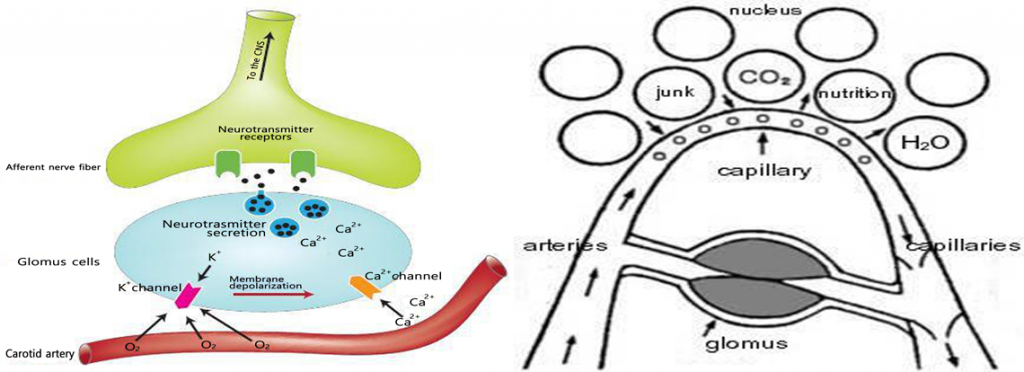

Glomus “The Glomus becomes paralyzed when blood clots obstruct the blood vessels. If this condition persists, the person is going to die. This new natural medicine treatment: GRF Medicine Restores your cell vitality and improves the quality of life. The usual wear and tear of our primary organs (kidney, stomach, liver, lung, heart). During the average lifetime of seven decades, our body grows old, and the average life of 80 to 85% of capillaries is damaged. We have 40 billion capillaries throughout our body (100,000 miles). “Glomus is the gateway to the blood, oxygen, nutrients and waste/sludge removal. Glomus is the bodies emergency response system that is triggered during life threatening incidents. “Glomus is the gateway to our body’s system of supplying blood, oxygen, and nutrients.

“Glomus must be attached to each capillary”.

Blood from the heart circulates in the order of the aorta, arteries, veins and capillaries.

When this natural circulatory system has problems, the blood stops and loses its place to go any further. Finally, people will die. A pale complexion when shocked and frightened causes a rapid contraction of the capillaries. This is because the blood is temporarily blocked.

The capillaries are said to be about 1/7 of the hair. When blood passes through the capillaries

Red blood cells, white blood cells, platelets, and other types of ingredient’s flow in a row single file. At this time, impurities in the blood (pigment, uric acid, thrombus & blood) cannot flow and capillaries If the tube is blocked, the glomus will become functionally disrupted within a few weeks. Cell tissues under these capillaries are more likely to stop nutrient supply and the problem is that hemoglobin in the red blood cells cannot supply oxygen, so the cells cause complications in proper functioning of body immune systems, leading to serious diseases including cancer.